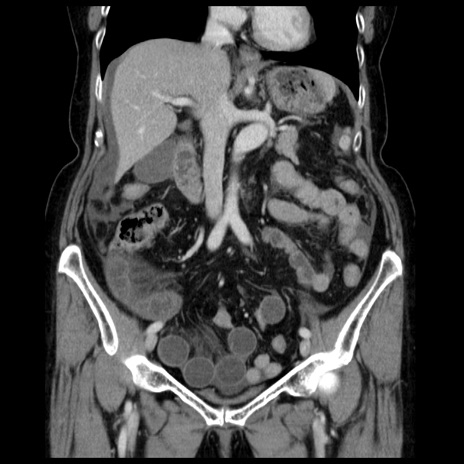

症例13(冠状断像)

【症例】70歳代女性

【主訴】腹痛、嘔吐

【現病歴】15時間程前(昨晩)より腹痛あり。今朝になっても症状の改善なく、嘔吐あり。腹痛も増悪あり、救急外来受診。

【既往歴】子宮癌全摘術後

【身体所見】意識清明、BP 121/72mmHg、P 74bpm、SpO2 100%(RA)、腹部:平坦・軟、腸雑音ほぼ聴取せず。下腹部・心窩部・臍左上に圧痛あり。反跳痛なし。

【データ】WBC 10600、CRP 0.15